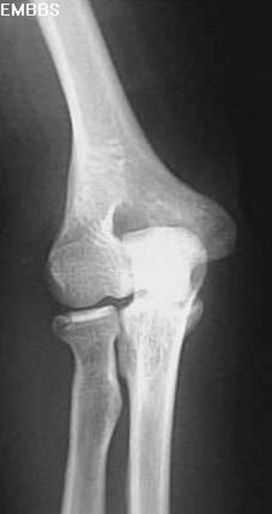

正常肘关节

肘关节脱位

肱骨髁上骨折